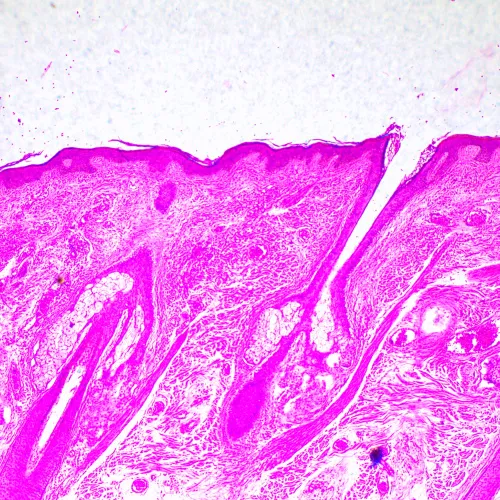

Изследователски клас микроскоп. Конструиран за наблюдение на прозрачни и полупрозрачни биологични проби, като например натривки и напречни сечения в преминаваща светлина по метода на светлото поле. Монтирането на допълнителни принадлежности ще осигури възможност за използване на методите на тъмното поле, фазовия контраст, диференциалния интерферентен контраст, флуоресценцията и поляризацията.

Микроскопът е подходящ за микробиологичен анализ, медицински диагностики и решаване на научни и изследователски проблеми.

Фазовоконтрастни устройства, флуоресцентно приспособление, кондензери за тъмно поле, устройства за поляризация и DIC устройства увеличават контрастните методи и позволяват изучаването на обекти, невидими в светлото поле.

- Наблюдение на прозрачни и полупрозрачни образци по метода на светлото поле с пропусната светлина